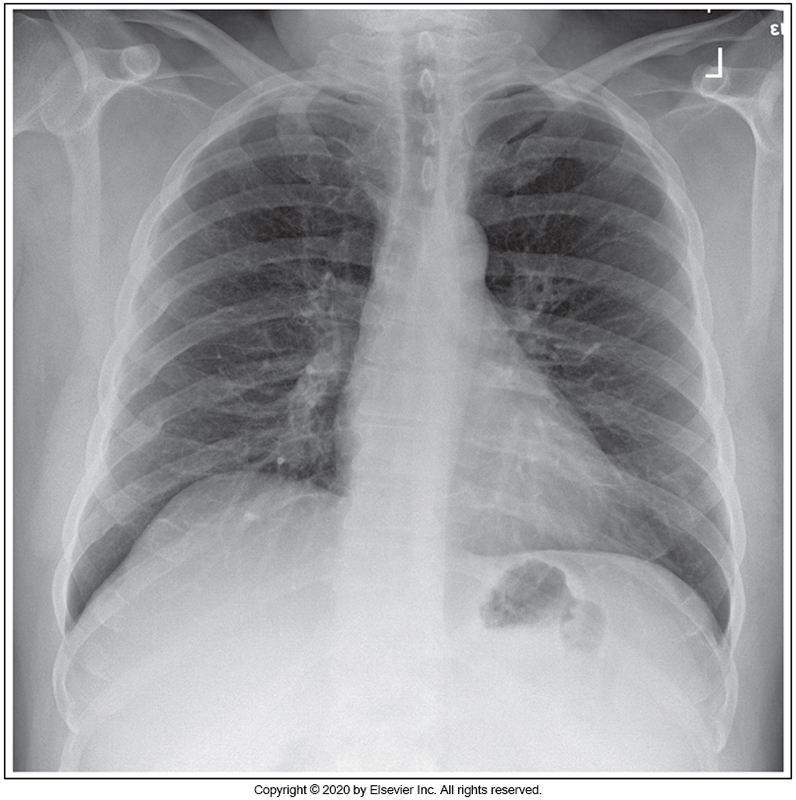

Identify the main problem of the image below (PA chest)

Patient is tilted anteriorly.

Patient is rotated.

Image taken on expiration.

Patient is tilted posteriorly.